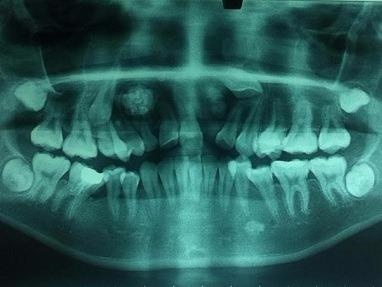

| Mỗi lần muốn uống nước hay nói chuyện, bà Liu phải lấy tay nâng khối u của mình lên. Ảnh: Asia Wire. |